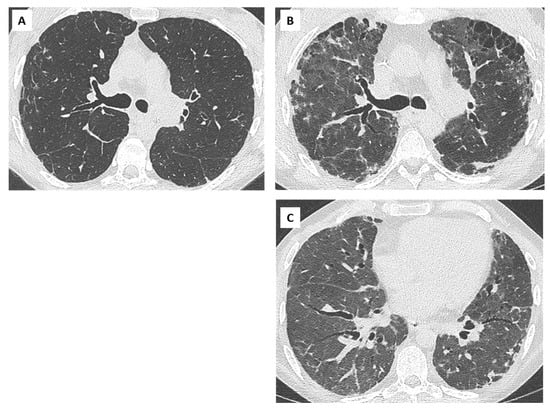

4. Bronchiolitis Obliterans Syndrome